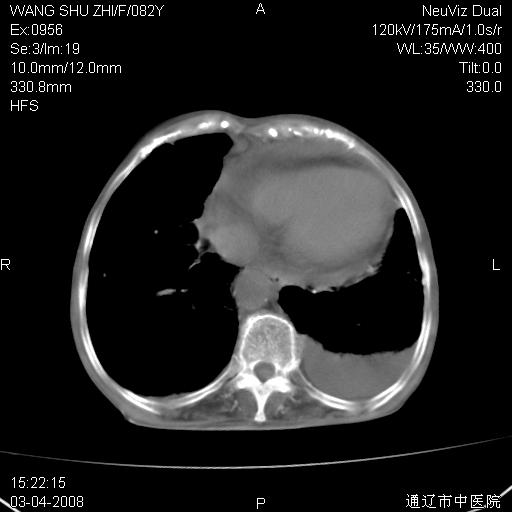

该患者为女性,82岁,既往肺心病、心衰病史。上纵隔影增宽,是否为畸形扩张的血管呢?因该患者年龄太大,又有较严重心脏病,故不适宜做增强检查。

中纵隔肿块最多见是淋巴瘤,而且以hd为多见,呈侵袭性生长,纵隔脂肪间隙消失,再加上心包和双侧胸腔积液,考虑为淋巴瘤(hd)应该说比较准确的。至于说是畸形的血管可能性小,因为畸形血管周围脂肪间隙应该存在。

纵隔淋巴结转移或淋巴瘤;双侧胸腔积液,心包积液。肺窗呢?

病史太简单,年龄太大,首先考虑转移!左侧腋窝亦见肿大淋巴结。

左侧腋窝及纵隔内见多个肿大淋巴结影,左侧少量胸腔积液,心包积液,支持淋巴瘤可能性大,不除外淋巴结转移。